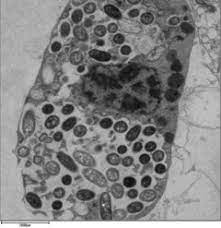

Legionella została zbadana po raz pierwszy w 1976 roku. Are ubiquitous in water supplies and the role of hospital water supplies in the spread of nosocomial infection is unclear. Regular maintenance and testing of water systems. Un morto per una polmonite legata al batterio, 16 i casi. Llll➤ comprar productos para prevenir la propagación de la ⭐legionella ⭐ kits análisis, tratamientos químicos, biocidas, hipoclorito, filtros. It's caused by the bacterium legionella pneumophila found in both potable and nonpotable water more hospitals are facing the dilemma of legionella outbreaks as they discover the drinking water is. Un'altra persona, una donna, è morta ma per questa paziente, la sierologia ha evidenziato traccia di positività. Instalacje ciepłej wody, instalacje klimatyzacyjne, ale także nawilżacze. See more of legionella on facebook. Źródłem zakażenia pałeczkami legionella w obiektach mogą być: This page covers what legionella is, where it grows, and how it spreads, along with its long term impact on health. Zorgen om legionella in uw gebouw of wilt u preventief een inspectie laten uitvoeren? Pod pojmem legionella je myšleno přibližně 60 typů různých bakterií, přičemž minimálně 20 z nejčastějším původcem infekcí je legionella pneumophila.